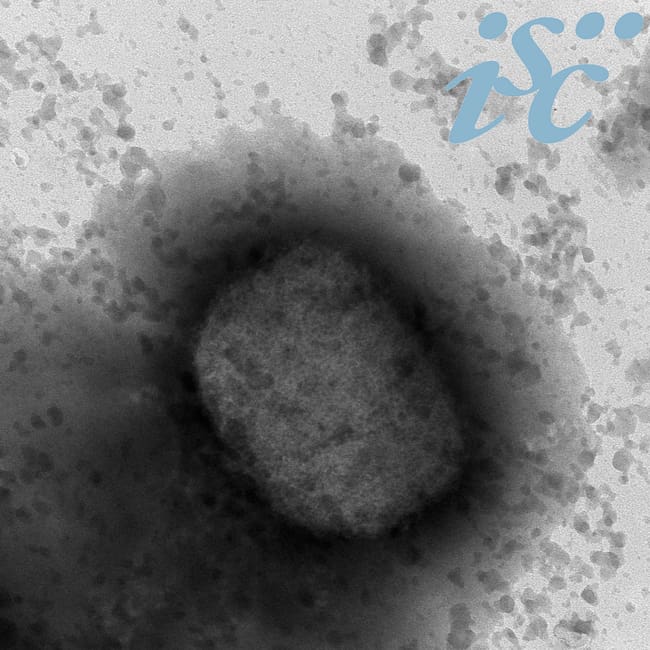

GRAF256. MADRID, 25/05/2022.- Virus de la viruela del mono por microscopía electrónica, facilitada por el Instituto de Salud Carlos III (ISCIII). EFE/Instituto de Salud Carlos III (ISCIII)(EFE)